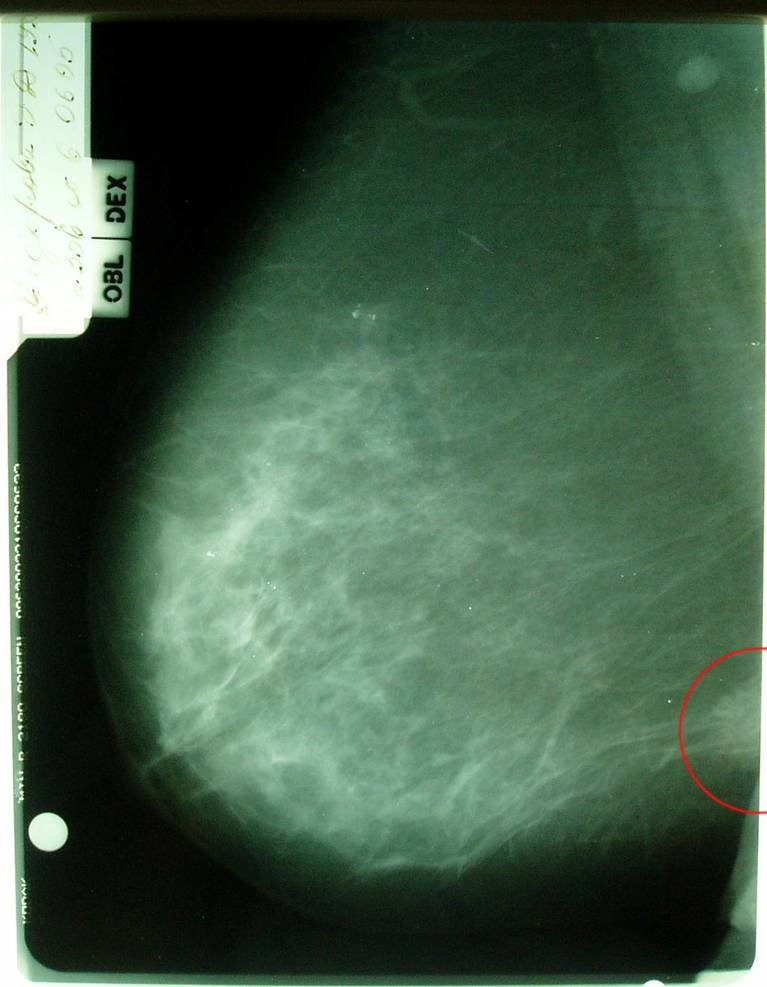

Маммограмма в динамике.

Больная раком правой молочной железы T4аN0M0. Регресс.

12.09.2005 (после лучевой терапии)